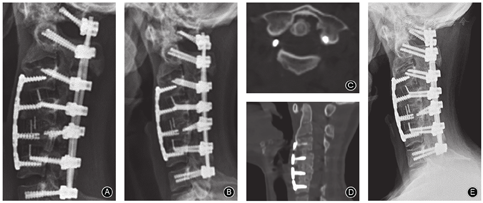

患者取仰卧位,取右侧斜切口。"C"型臂X线机透视确定椎间隙,行C3,4、C4,5、C5,6椎间隙松解,磨钻去除椎间隙前方骨赘及椎间骨性融合部分,找到椎间隙,切除椎间盘并松解两侧钩椎关节。术中正确找到椎间隙,松解过程中减少对骨性终板的破坏,对通过良好支撑获得满意的颈椎前凸重建,减少椎体塌陷导致矫正丢失至关重要。术中牵引用撑开器对松解的椎间隙逐一撑开后,可见颈椎活动度较前好转,后伸活动范围增大,再次透视确认颈椎后凸较松解前有改善(图4A,B)。

敷料包扎切口后将患者置于俯卧位,取后正中切口。显露C1~C7棘突锥板及关节突关节,探查可见后方椎板间关节突关节融合,此时,通过颈椎后方外侧找到椎间孔外缘,确认小关节关节突、椎间孔和椎板间隙是顺利实施Schamb 2级截骨的关键。磨钻在后弓与枕骨之间分离寰枕间隙并去除椎板间骨质,并使后弓得以完整保留。分别植入寰椎侧块螺钉和C2~C7椎弓根螺钉,去除C4~C6部分椎板及两侧关节突。寰椎后弓与枕骨松解、分离,不仅可以获得较好的寰枢椎复位,而且是枕颈关节的功能得以保留的保障。安装连接棒,由台下助手通过颅骨牵引弓牵引状态下逐渐后仰患者头部使寰椎复位、颈椎后凸得到改善,并逐渐锁紧钉棒系统,完成后路矫正。术中透视见寰枢椎复位、颈椎后凸畸形矫正满意,脊髓无明显皱褶(图4C)。术中脊髓监护未见异常,术中唤醒患者上、下肢活动良好。制作植骨床并植骨。

再次翻身后患者置于仰卧位,行C3,4、C4,5、C5,6行颈前路椎体次全切除减压融合术(anterior cervical corpectomy decompression and fusion,ACDF),cage支撑植骨融合内固定术增加前柱支撑。前路钉板系统固定,进一步完成颈椎畸形矫正及前凸重建,术中透视见恢复颈椎前凸(图4D)。

术后第2天佩戴颈托下地活动,四肢活动良好,无麻木疼痛不适等。术后1、3、6、12和48个月随访。术后1年随访颈椎前凸Cobb角丢失2.7°;椎间植骨融合良好,后路植骨有部分吸收;术后随访寰齿前间隙和寰齿侧间隙较术前明显改善(图5)。内固定位置好,未见松动与断裂。术后1年,患者JOA评分为17分,NDI为14%,ASIA分级E级。

术后4年随访,患者颈椎ROM为前屈45°、后伸10°、左侧屈30°、右侧屈30°。